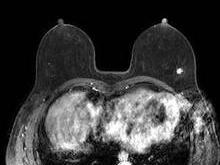

乳腺错构瘤(hamartoma of mammary gland)是由脂肪组织、纤维组织、乳腺导管和乳腺小叶多种组织成分混合生长而成,是临床上比较少见的特殊类型的乳腺良性肿瘤。